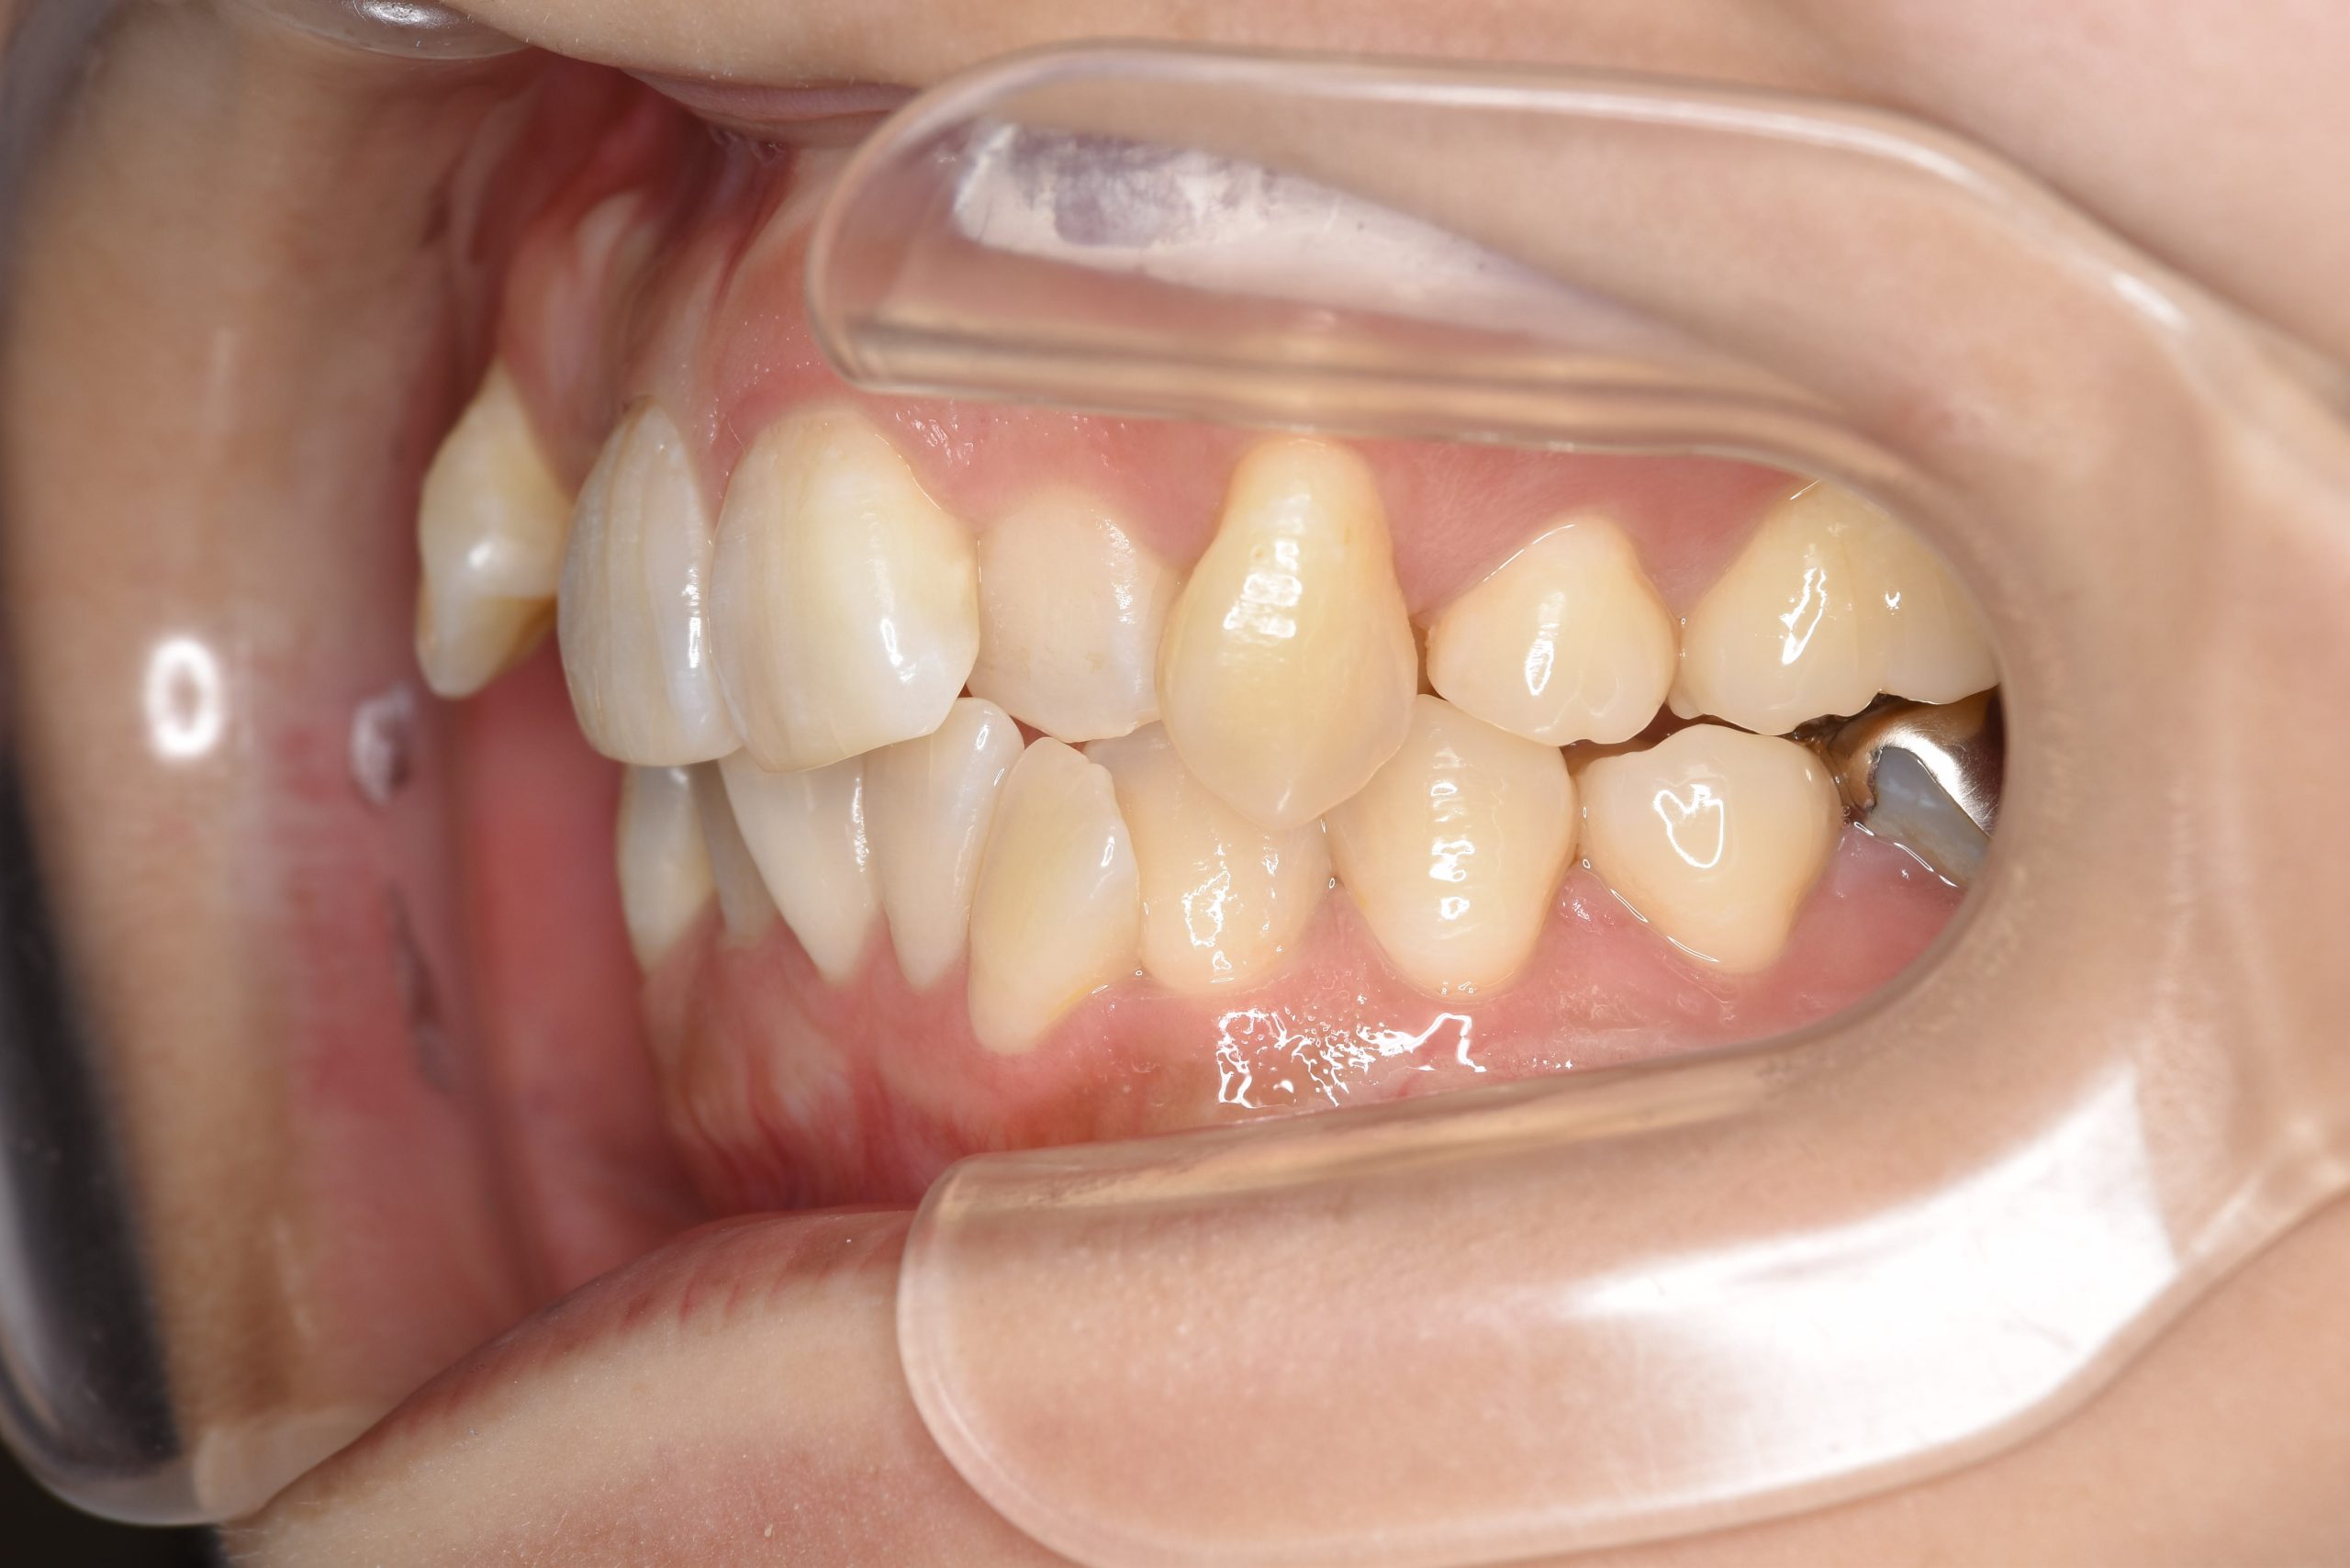

ビフォー

主訴 八重歯

施術内容 MSEと下顎リンガルアーチを用いて上下顎骨を拡大した。

その後上顎3・4番を抜歯しマルチブラケット装置とミニインプラントを用いて

歯牙を配列した。良好な咬合を獲得した。

治癒期間 1年8か月間